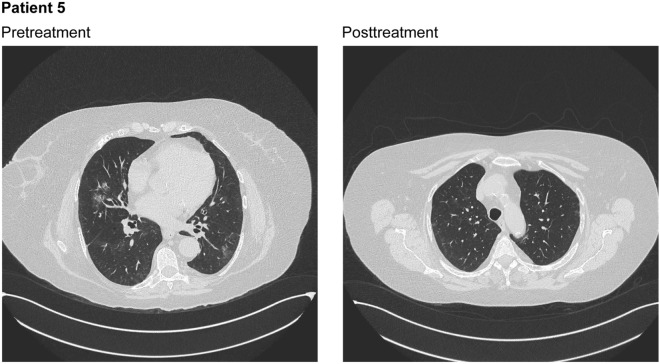

The patient was admitted to the hospital on December 26, 2020. Empiric treatment with antibiotics (Table 2) provided limited improvement. On January 21, a nasopharyngeal swab tested positive for SARS-CoV-2, and a chest CT scan without contrast showed focal ground glass areas, mainly located in the upper lobes bilaterally, with the largest in the medial area of the middle lobe (Fig. 5). There were no signs of interstitial thickening and no evidence of lymphadenomegaly in the mediastinal area. These findings were considered consistent with COVID-19 interstitial pneumonia and grossly affected 5–10% of the lung parenchyma. A serology test for SARS-CoV-2 antibodies was positive. The patient was enrolled in the compassionate use study and treated with nebulized ribavirin from January 21 through January 27. On day 3 of ribavirin aerosol therapy, a nasopharyngeal swab again tested positive for SARS-CoV-2.

Fig. 5.

Chest computed tomography scans without contrast for patient 5 at pretreatment, showing focal ground glass areas, mainly located in the upper lobes bilaterally, with the largest in the medial area of the middle lobe, and posttreatment, showing almost complete resolution of the ground glass thickening in the parenchymal area, with only a few areoles persistently and slightly thickened

A CT scan performed on February 1 showed complete resolution of the ground glass thickening in the parenchymal area, with only a few areoles persistently and slightly thickened (Fig. 5). On February 3 (1 week after the last dose of ribavirin aerosol), viral clearance was verified with a negative nasopharyngeal swab. The patient was discharged from the hospital on February 4 in good clinical condition. At the end of quarantine, two sequential nasopharyngeal swabs for SARS-CoV-2 yielded negative results.